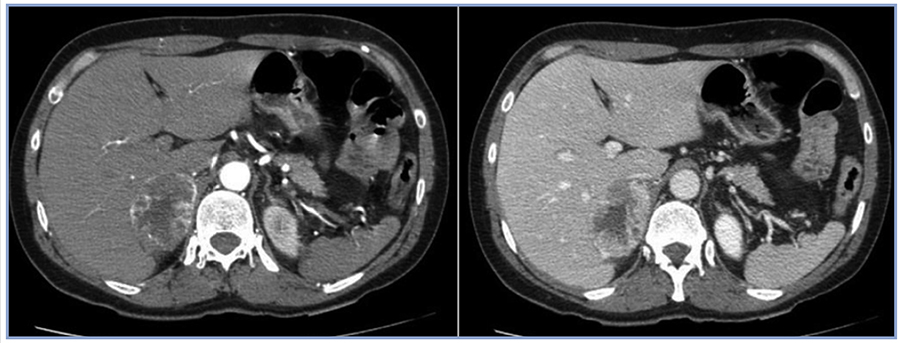

Consultó en urgencia por cuadro de dolor retroesternal de inicio agudo, opresivo, irradiado a dorso, diaforesis y palpitaciones. A su ingreso destaca: presión arterial (PA) 214/120 mmHg, frecuencia cardiaca (FC) 126 x min, mala perfusión, somnolencia y manchas café con leche. Las enzimas cardiacas mostraron valores normales. El ECG reveló supradesnivel de ST y T negativas de V2 a V4, con Q patológica en V5-V6-DI y AVL. Coronariografía: Coronarias sin lesiones, hipokinesia difusa con fracción de eyección (FE) de 20%. Interpretándose como miocardiopatía de Takotsubo (MTT) (Figura 1). En base a los hallazgos con alta sospecha de feocromocitoma, se solicita metanefrinas urinarias totales: 6,3 mg/24 h (VN: 0-1), TSH 2,32 uIU/ml PTH: 46,1 pg/ml Ca 9,5 mg/ dl, P: 4 mg/dl, Alb: 4,3g/dl Calcitonina basal: 4,8 pg/ml (VN: < 4). Ecografía renal descartó estenosis de arterias renales con masa renal sugerente de neoplasia. TC con contraste: masa suprarrenal derecha de 6,3 cm de eje mayor con características de feocromocitoma (Figura 2).

Figura 2. A: fase arterial; B: fase.